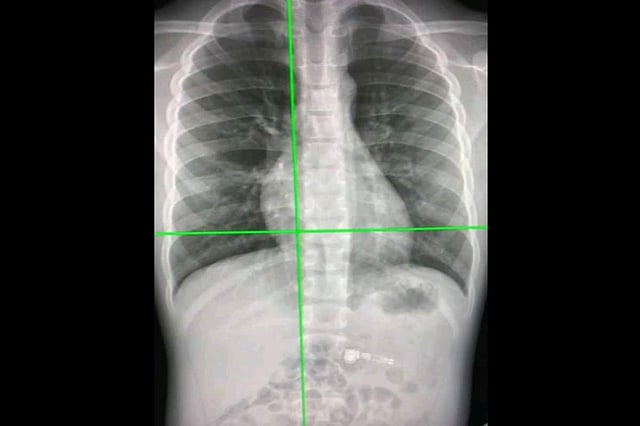

Australian researchers have developed an artificial intelligence (AI) system that can rapidly detect COVID-19 from chest X-rays with more than 98 percent accuracy and may be more beneficial than the currently used RT-PCR test. According to Professor Amir H. Gandomi from the University of Technology Sydney (UTS) Data Science Institute, there was a pressing need for effective automated tools to detect COVID-19, given the significant impact on public health and the global economy.

Common symptoms of COVID-19 include fever, cough, difficulty breathing, and a sore throat, but it can be difficult to distinguish COVID-19 from flu and other types of pneumonia. The new AI system, detailed in a paper published in the journal Scientific Reports, uses a deep learning-based algorithm called a Custom Convolutional Neural Network (Custom-CNN) that is able to quickly and accurately distinguish between COVID-19 cases, normal cases, and pneumonia in X-ray images. "Deep learning offers an end-to-end solution, eliminating the need to manually search for biomarkers. The Custom-CNN model streamlines the detection process, providing a faster and more accurate diagnosis of COVID-19," said Professor Gandomi.